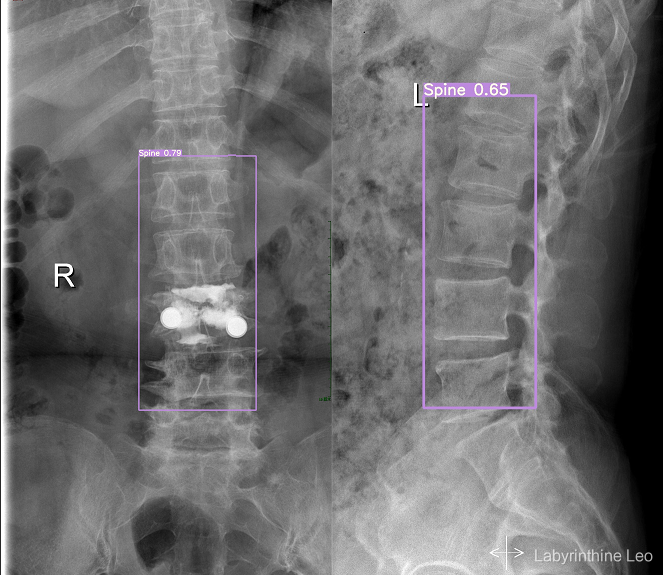

这样设置完毕后,训练是命令同样将--data参数设为--data ./data/my_datasets.yaml即可,自己的训练代数尽量设置大一些才会出现效果(博主训练了300个epochs)。接下来的预测、可视化过程同上,此处不赘述。预测效果如下: